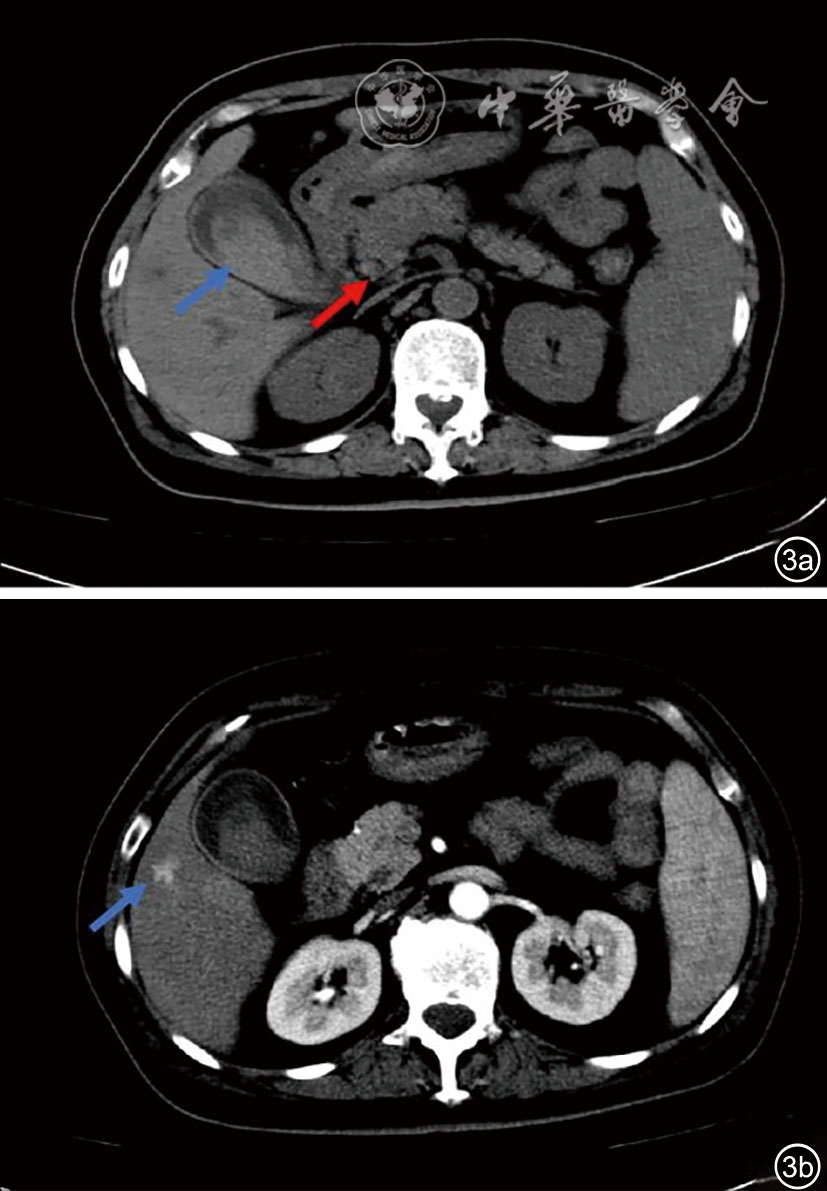

图1 自身免疫性肝炎合并肝结节的上腹部MRI增强(肝特异性造影剂)图像及二维超声图像、超声引导下穿刺活检图像。图a示肝胆期肝内多发高摄取信号结节(蓝色箭头);图b为二维超声示肝内多发微小稍高回声结节,较大者长径约7 mm,境界尚清,形态尚规则;图c为超声引导下经皮肝穿刺活检,选择右侧肋间隙第8肋间进针,由前外侧向后内侧,在彩色多普勒超声引导下避开主要血管、大胆管及胆囊